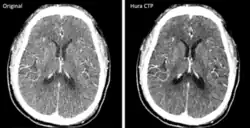

The development and FDA clearance of photon-counting detectors (PCD) for computed tomography (CT) scans in 2022 was an important innovation. These detectors offer a more efficient process for converting X-rays to electrical signals, allowing for better material differentiation and potentially reducing the radiation dose for patients. The image to the right shows two scans of the same brain using old and new CT technology respectively.[24]